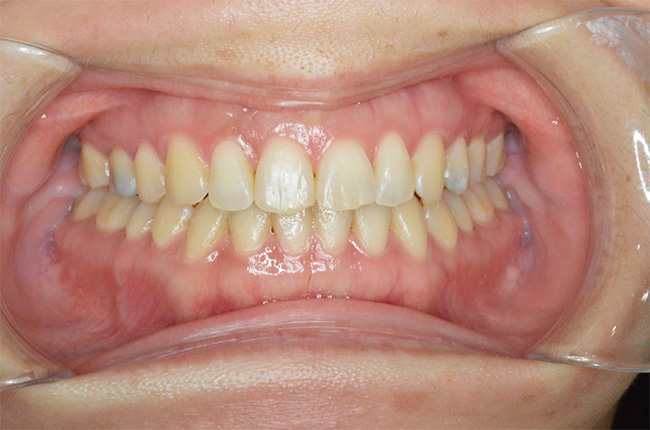

治療終了時